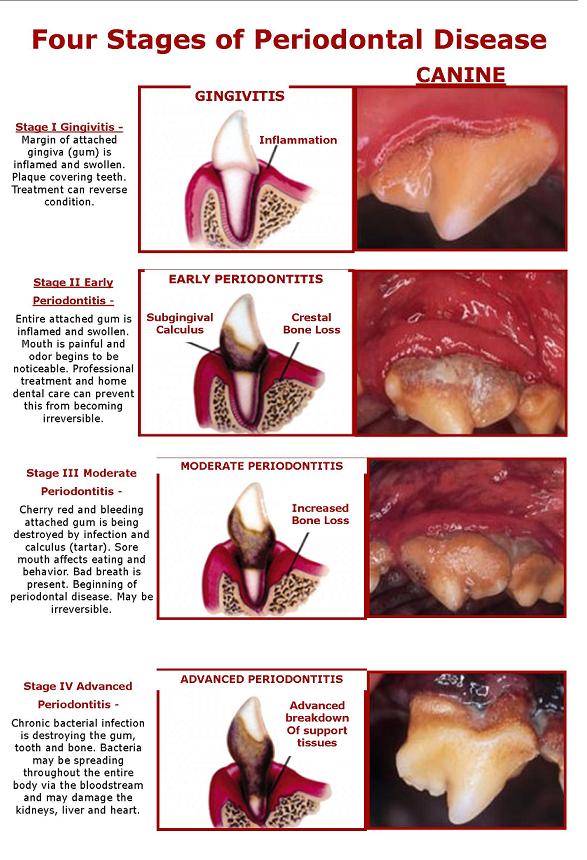

What is periodontal disease?

What are periodontal diseases? Periodontal disease is an infection in the areas around the teeth, but not in the teeth. Gingivitis is usually the first stage of periodontal disease which can progress and effect other structures in the mouth.

What is the first stage of periodontal disease?

The first stage of periodontal disease, called gingivitis, only affects the gums. Symptoms of gingivitis may include bleeding and swollen gums, bad breath, pain when chewing, and recession of the gums. If left untreated, gingivitis can advance to the other structures in the mouth and overtime, cause tooth or bone loss.

How many phases of periodontal disease?

Treating periodontal disease is usually broken down into three phases. The first phase is focused on minimizing the risks that may have caused the infection, controlling the infection, and learning how to take care of your oral care to stop the progression of the infection.

According to the National Institute of Dental and Craniofacial Research, it’s caused by poor oral hygiene, smoking, chronic illnesses or using certain medications.

Because periodontal disease can increase your risk for conditions such as stroke, heart disease, diabetes, and respiratory diseases, it’s critical to treat it. Starting the treatment early can help you avoid requiring the more invasive treatments later on.

Is periodontal disease a bone disease?

This can include the gums , tissues, and/or bones of the mouth.